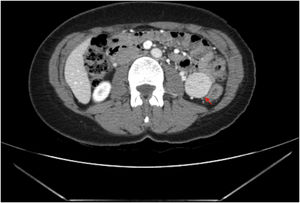

A 46-year-old woman, with intermittent colicky abdominal pain, was diagnosed of an intraperitoneal tumor in an abdominal tomography (Fig. 1), oriented as a gastrointestinal stromal tumor.

Abdominal contrast-enhanced computed tomography: 32 × 32 × 34 mm homogeneus hypervascular well-defined solid tumor with a small central hypodensity (red arrow) located in the intraperitoneal left posterior abdominal void, with an apparent intraperitoneal location. The dependency organ is not defined, only broad contact is seen with adjacent intestinal loops but without thickening or stenosing them.